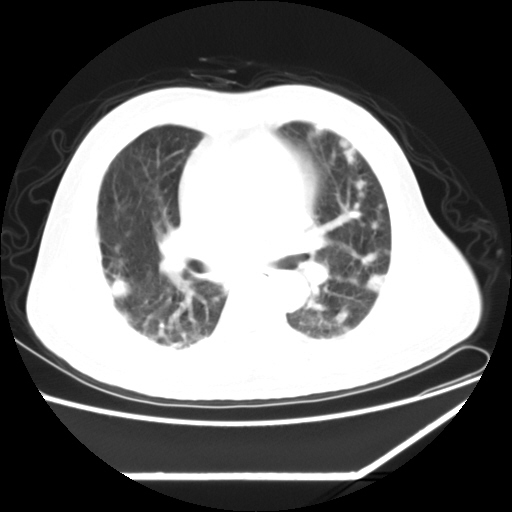

男,57,畏寒,发热

双肺多发结节样病灶,部分内见透光区,纵隔内见淋巴结肿大。结核临床如有畏寒,高热,白细胞增高首先考虑迁徙性肺脓肿(多是金黄色葡萄球菌感染)。

注意除外转移瘤。

1)考虑两肺感染性病变(金黄色葡萄球菌肺炎?);建议抗炎治疗后复查排除其他。2)双侧少量胸腔积液。

双肺典型的亚急性粟粒性肺结核

双侧胸膜结核